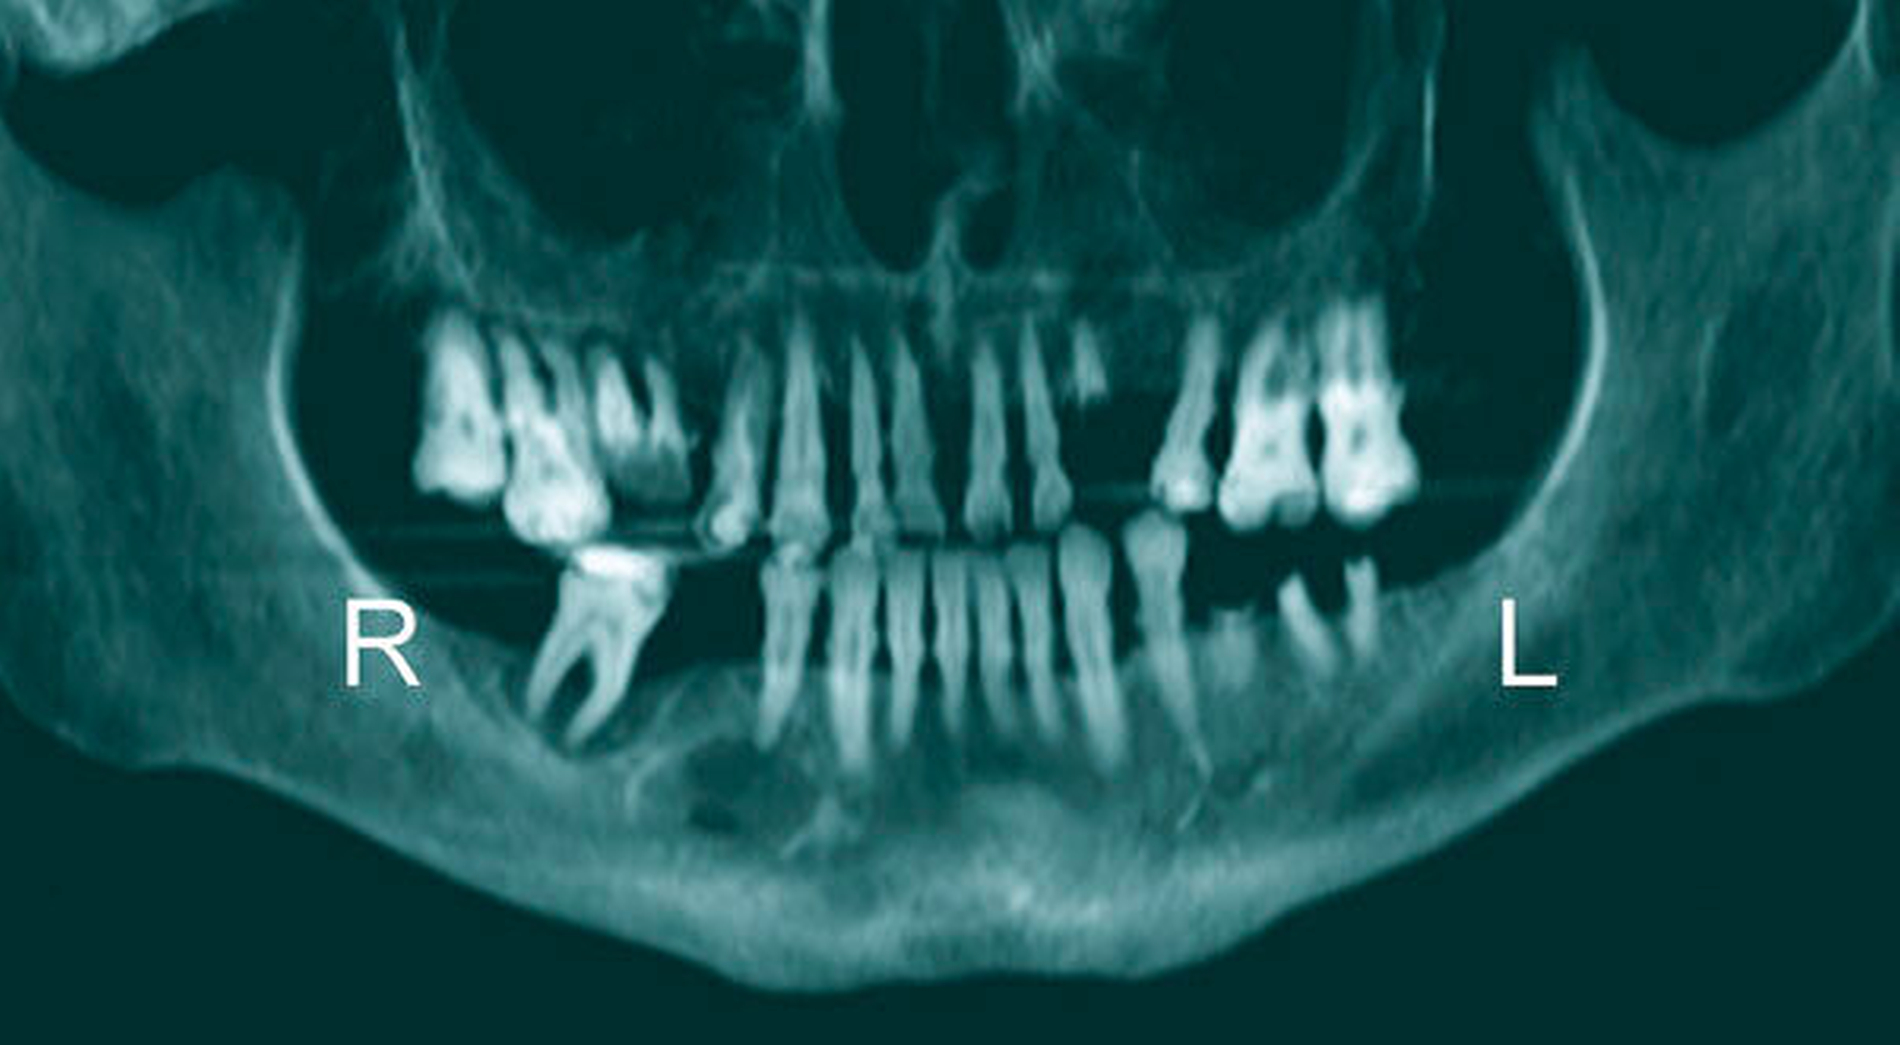

Der Patient gab an, dass er wegen Schmerzen und Schluckbeschwerden seit Tagen nicht mehr essen und trinken könne. In der klinischen Untersuchung imponierte eine massive Schwellung und Rötung des gesamten anterioren und lateralen Halses. Der Zahnstatus war klinisch mit multiplen zerstörten Zähnen und Wurzelresten desolat (Abbildung 1).